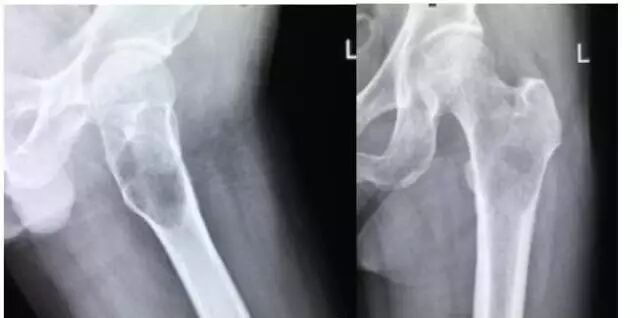

MM引起的骨病变

一般而言,MM 不能早期诊断、易误诊的重要原因是:对化验检查发现的球蛋白或贫血等异常结果疏于重视,对临床表现及化验检查缺乏全面正确分析。另外,部分患者不愿接受骨髓检查也会延误病情无法尽早诊断。

1. 不明原因骨痛或病理性骨折;查体有骨压痛,扁骨有肿块者;早期截瘫症状(如下肢无力、排尿困难等)。

MM引起的病理性骨折